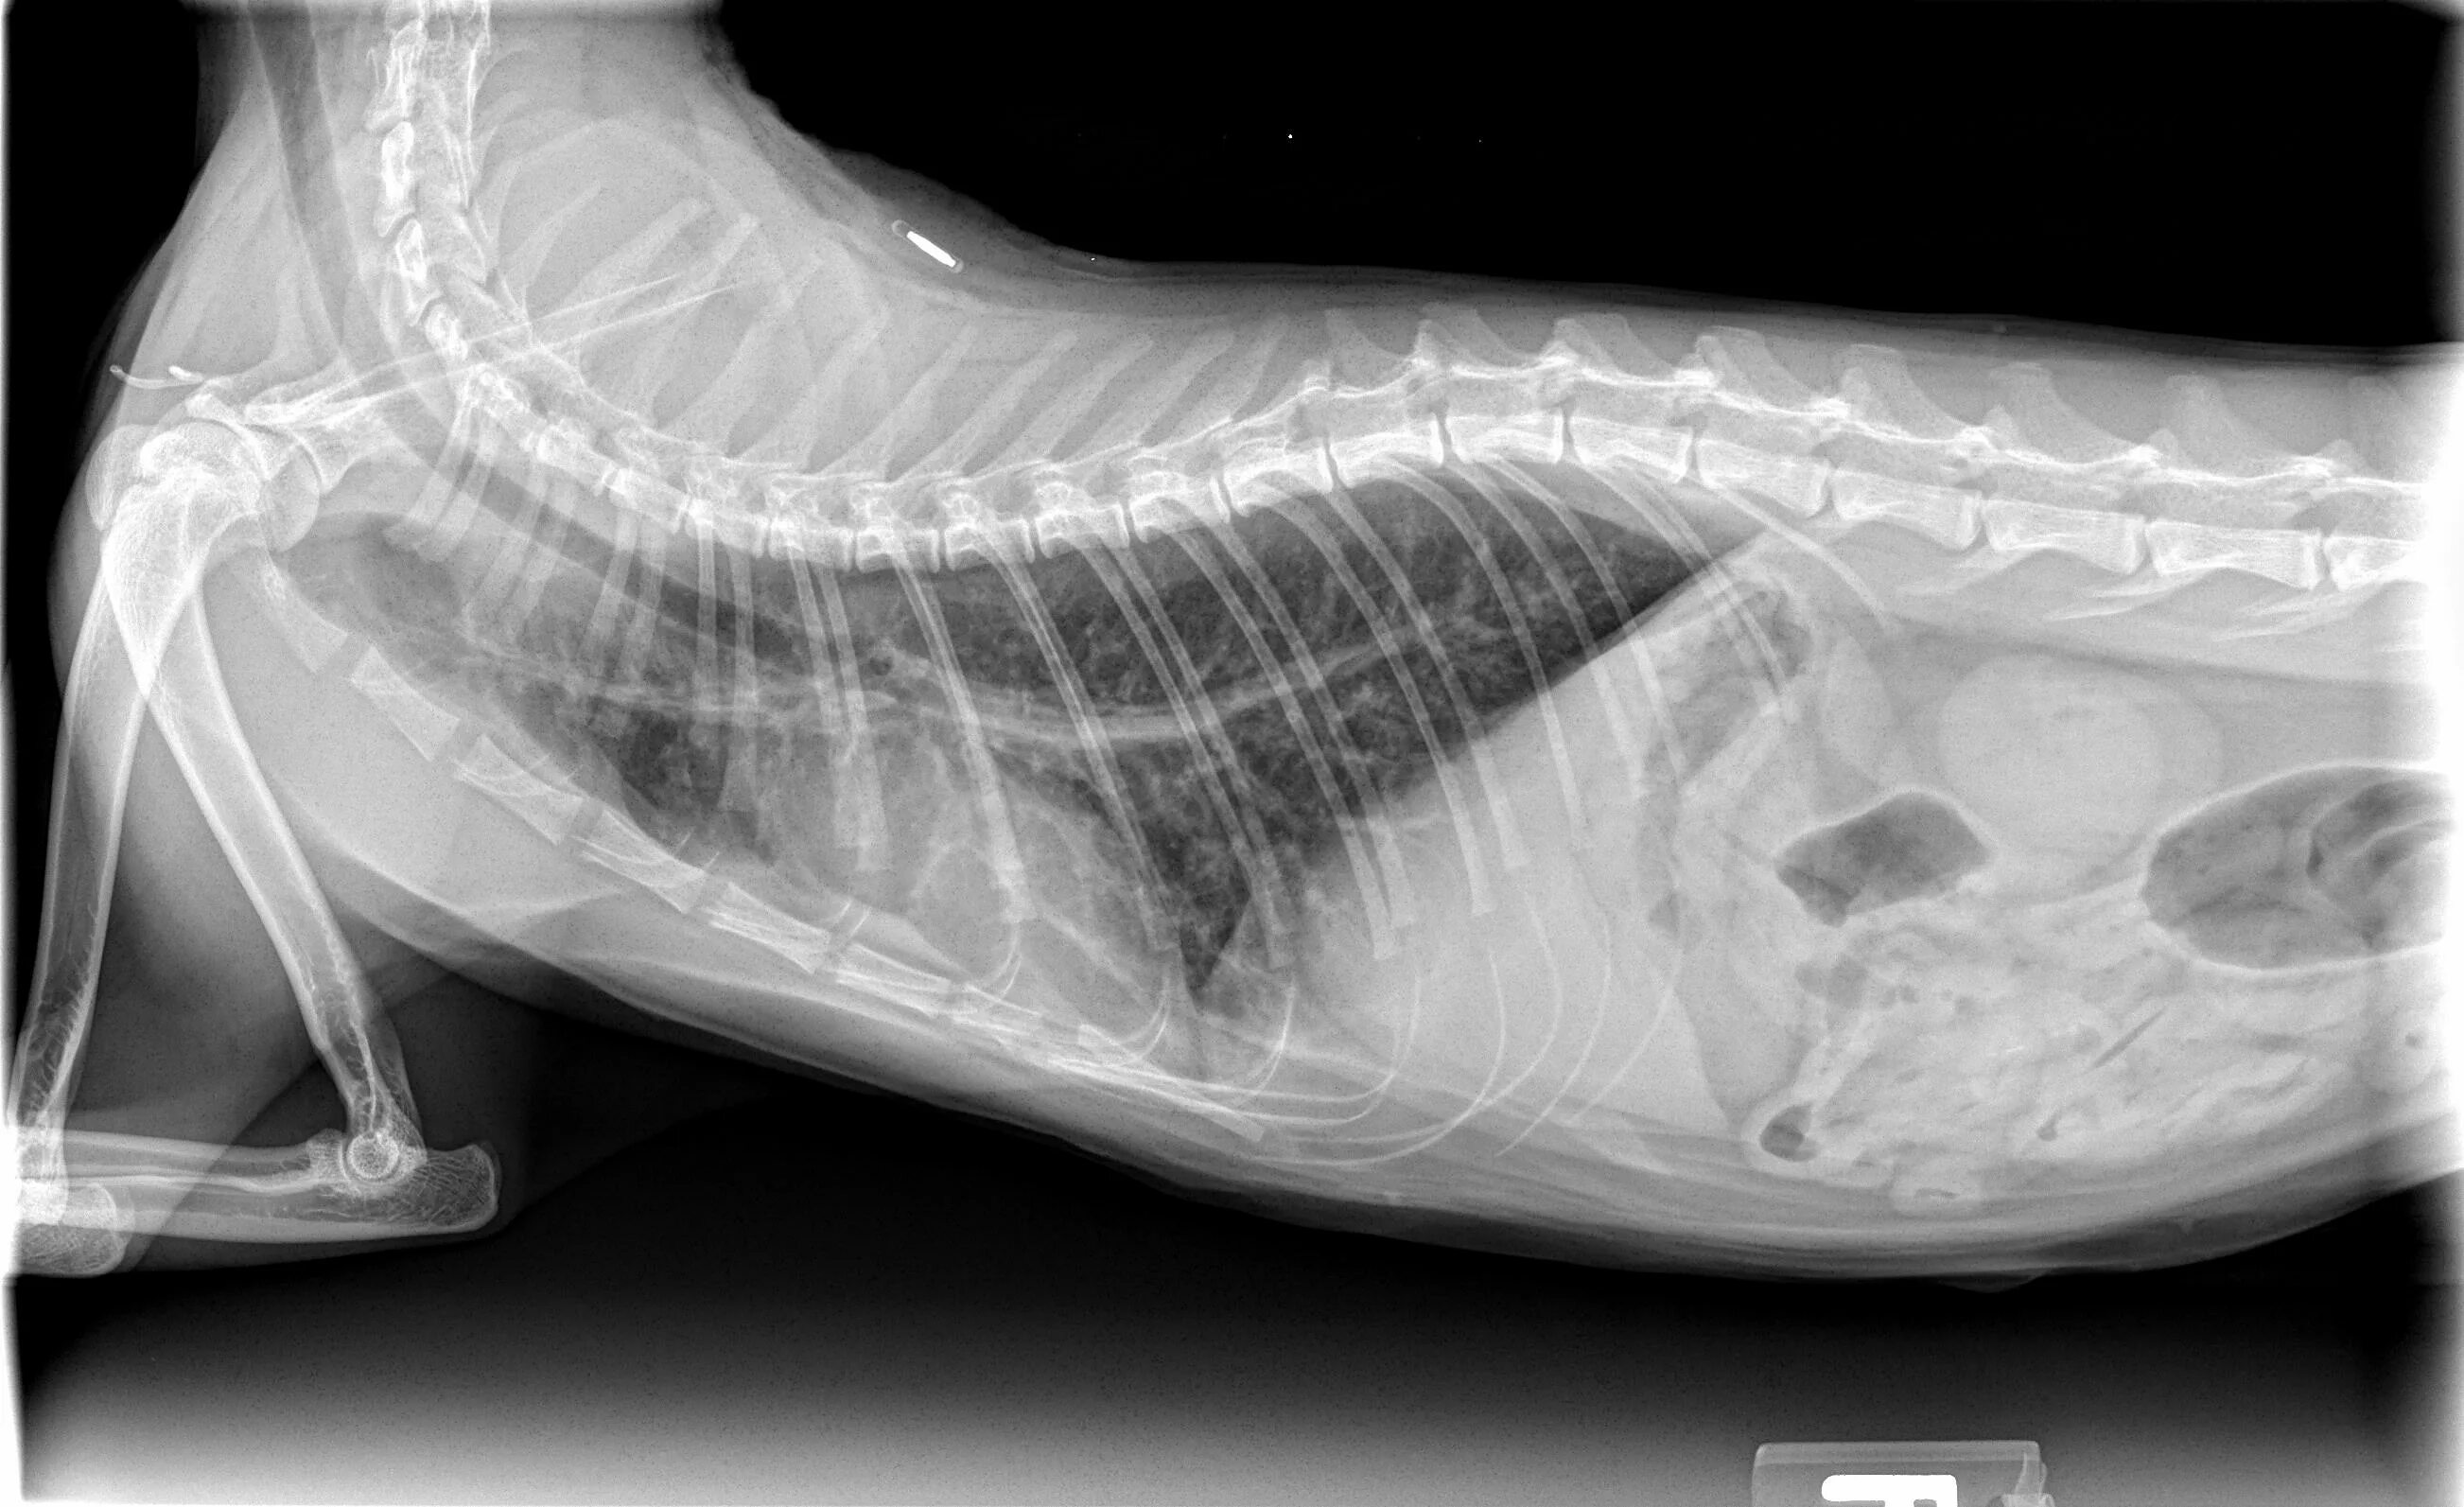

Астма у кота